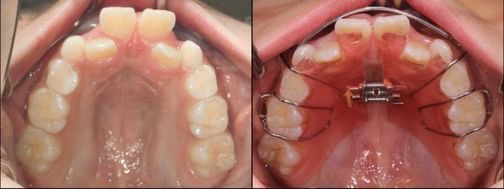

混合歯列から拡大装置を使用し、ワイヤーでの矯正に移行した症例。

天然歯を抜歯することなく、歯列不正を改善できた。

(左上は初診時、右上は拡大床セット時、左下は永久歯列に移行した時期、右下現在)